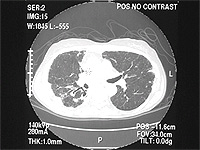

A 50 yo male was receiving home IV antibiotics for osteomyelitis of his hip. He was 7 weeks into his course of therapy when he began to develop low grade fevers. Over the next 2 weeks extensive work-up was done without revealing a source for the fever. The orthopedics service felt his osteomyelitis was responding to the therapy and that this was unlikely a source for his elevated temperature. About this time he began to experience dyspnea, which progressively worsened so he was admitted to the hospital for evaluation. Physical exam revealed T 100.8, R 16, P 82, BP 130/74; Right subclavian tunneled catheter; Lungs with scant bibasilar rales; CV with regular rhythm and no murmur; Extremities without cyanosis, clubbing, or edema. PFTs: FVC 3.98 L (83% predicted); FEV1 3.08 L (80% predicted); TLC 5.74 L (85% predicted); and DLCO 14.96 ml/min/mmHg (42% predicted).

CXR showing multiple nodules.

CT showing multiple small nodules

Diagnosis: Pulmonary Talcosis